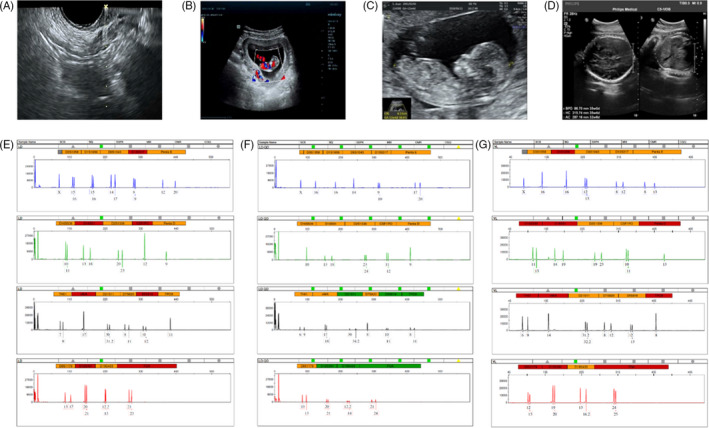

取卵和妊娠特征

收集了15名接受取卵的患者的基本特征,包括取卵周期、胚胎移植和妊娠次數。一般來說,四個胎兒沒有出生缺陷,三個胚胎來自ICSI的受精類型,而最后一個是自然受孕的。1例術中超聲掃描顯示,在經陰道超聲(TVUS)引導下,卵巢未見間質增生或其他異常卵巢結構(圖2A)。這名婦女在體外受精后成功懷孕,并在第8周進行了基本產前程序的超聲掃描(圖2B),第13周(圖2C) 和第32周 (圖二維) 顯示正常的胎兒發育。微衛星位點分析顯示,胎兒(圖2F)與母親有遺傳關系(圖2E) 供體UCMSC以外的其他人(圖2G)。

圖2:妊娠和新生兒結局。(A)超聲掃描顯示USMSCs移植過程中有穿刺過程;(B-D) 孕周 8 周 (B)、13 周 (C) 和 32 周 (D) 妊娠患者的超聲檢查;(E-F) 母血(E)、胎兒臍帶(F)和供體細胞(UCMSCs)(G)的微衛星位點分析